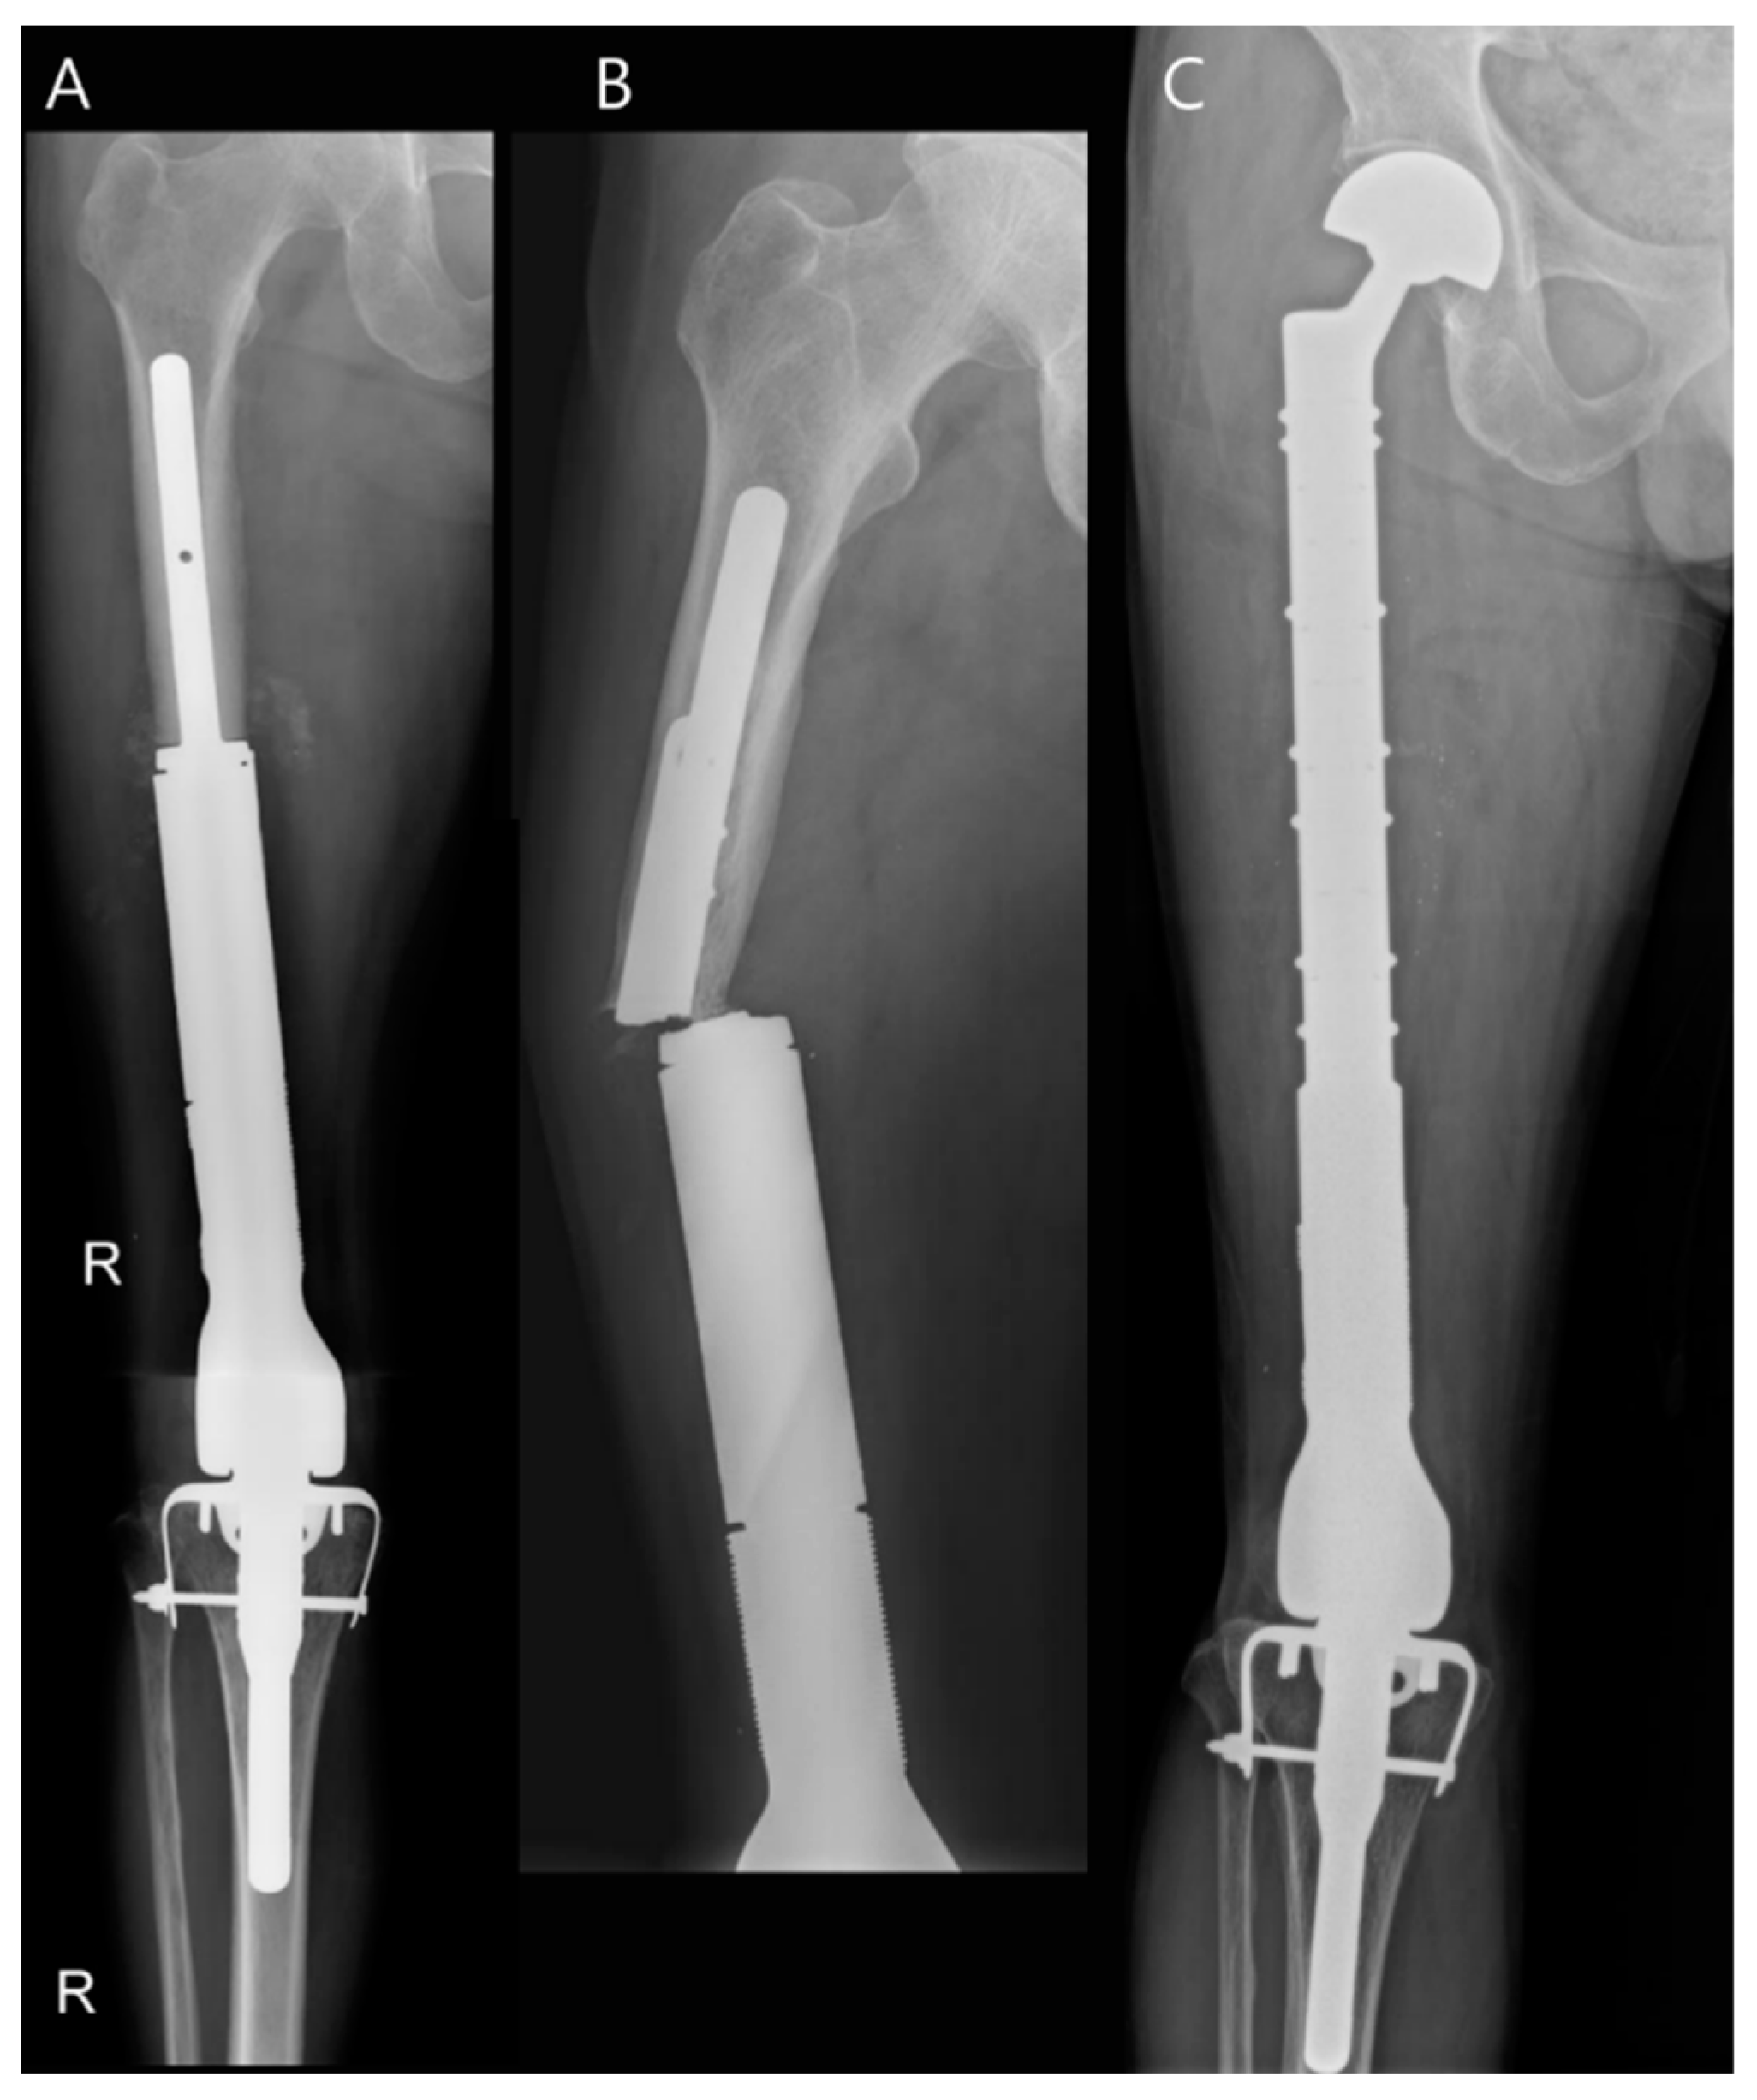

- Kim, H.-S. Endoprosthetic Reconstruction in the Limb Salvage Surgery for Treatment of Malignant Bone Tumors. J. Korean Orthop. Assoc. 2015, 50, 453–461. [Google Scholar] [CrossRef]

- Jeys, L.M.; Kulkarni, A.; Grimer, R.J.; Carter, S.R.; Tillman, R.M.; Abudu, A. Endoprosthetic reconstruction for the treatment of musculoskeletal tumors of the appendicular skeleton and pelvis. J. Bone Jt. Surg. 2008, 90, 1265–1271. [Google Scholar] [CrossRef] [PubMed]

- Seeger, L.L.; Farooki, S.; Yao, L.; Kabo, J.M.; Eckardt, J.J. Custom endoprostheses for limb salvage: A historical perspective and imaging evaluation. Am. J. Roentgenol. 1998, 171, 1525–1529. [Google Scholar] [CrossRef] [PubMed][Green Version]

- Pala, E.; Trovarelli, G.; Calabrò, T.; Angelini, A.; Abati, C.N.; Ruggieri, P. Survival of modern knee tumor megaprostheses: Failures, functional results, and a comparative statistical analysis. Clin. Orthop. Relat. Res. 2015, 473, 891–899. [Google Scholar] [CrossRef]

- Henderson, E.R.; Groundland, J.S.; Pala, E.; Dennis, J.A.; Wooten, R.; Cheong, D.; Windhager, R.; Kotz, R.I.; Mercuri, M.; Funovics, P.T.; et al. Failure mode classification for tumor endoprostheses: Retrospective review of five institutions and a literature review. J. Bone Jt. Surg. 2011, 93, 418–429. [Google Scholar] [CrossRef]

- Shah, A.; Cardoso, F.N.; Souza, F.; Montreuil, J.; Pretell-Mazzini, J.; Temple, H.T.; Hornicek, F.; Crawford, B.; Subhawong, T.K. Failure Modes in Orthopedic Oncologic Reconstructive Surgery: A Review of Imaging Findings and Failure Rates. Curr. Oncol. 2024, 31, 6245–6266. [Google Scholar] [CrossRef]